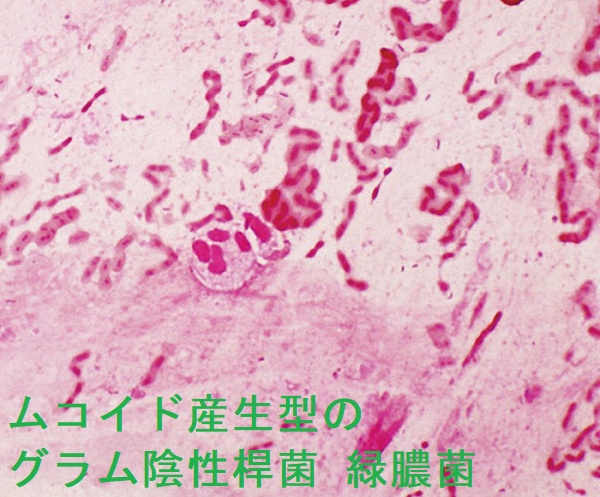

緑膿菌はムコイド産生型のグラム陰性桿菌で、医療・介護関連肺炎(NHCAP:nursing and health-care associated pneumonia)の起因菌でもある。Klebsiella pneumoniae(クレブシエラ・ニューモニエ、肺炎桿菌もムコイド産生型のグラム陰性桿菌であるが、微妙に形状が異なる。

甲状腺機能亢進症/バセドウ病治療に用いる抗甲状腺薬(メルカゾール、プロパジール、チウラジール)の最も恐ろしい副作用の一つが無顆粒球症です。無顆粒球症では緑膿菌(Pseudomonas aeruginosa )による敗血症を合併しやすい(無顆粒球症と緑膿菌感染 )[QJM. 1999 Aug;92(8):455-61.]。

甲状腺亜全摘術後に再発した甲状腺機能亢進症/バセドウ病女性で頬と脚の壊疽性潰瘍・蜂窩織炎(緑膿菌壊疽)をおこした報告があります[Int J Infect Dis. 2014 Apr;21:19-20.]。

緑膿菌による急性化膿性甲状腺炎の報告があります[Br Med J. 1977 Aug 27;2(6086):580.]。

緑膿菌は水場を好む菌です。緑膿菌毛包炎は、特殊な毛包炎で温水プール(循環式浴槽)、銭湯、プールのすべり台、サウナ、洗面台のスポンジ、ウェットスーツなどで感染します。

家族内感染をおこす事もあります。

普通の毛包炎は通常、表皮ブドウ球菌、黄色ブドウ球菌が原因です。緑膿菌性毛包炎は通常の毛包炎より痒み、痛みは強いが、見た目は同じで、緑色膿と違います。

第3世代セフェム、ニューキノロン系抗生物質内服、アミノグリコシド、ニューキノロン系抗生物質軟膏が有効。

免疫能が低下した場合、壊疽性膿瘍・緑膿菌壊疽(壊疽性膿皮症とは異なる)に進展することがあります。